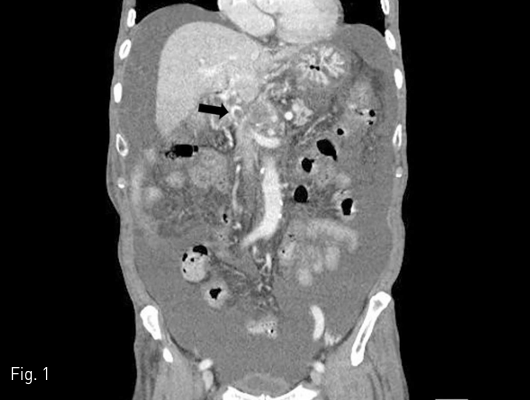

초음파 유도하 우측 경정맥을 천자하여 11 Fr sheath(Terumo, Tokyo, Japan)를 삽입하였고, 5 Fr angiographic catheter(Cook, Bloomington, Indiana)을 이용하여 간정맥 조영술 시행하였다. Transjugular intrahepatic portal access system (Cook)을 이용하여 우측 간정맥에서 우측 간문맥을 천자하여 간 문맥 조영술을 시행하였다. 간문맥 조영술에서 간문맥-장간막정맥 합류부에 심한 협착이 있었다 (Fig. 2). 이후 스텐트 진입을 위해 5 mm x 60 mm 풍선카테터 (Armada; Abbott Vascular, Santa Clara, California)를 이용하여 협착된 간문맥-장간막정맥 합류부와 우측 간정맥과 우측 간문맥 사이 간실질 통로를 혈관성형술을 시행한 후 10 mm x 68 mm self expandable bare metal stent (Wallstent; Boston Scientific, Natick, Massachusetts)를 주요 간문맥에서 상장간막정맥까지 설치하였다. 이후 8 mm x 40 mm 고기압 풍선카테터 (Conquest; Bard, Covington, Georgia)를 이용하여 다시 혈관성형술을 시행하였다 (Fig. 3). 이후 시행한 간문맥 조영술에서 간향성의 혈류가 회복되었다(Fig. 4).

Fig 4

Follow-up portogram shows favorable patency from the superior mesenteric vein to main portal vein.